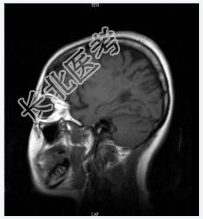

- [材料题] 患者女,28岁,反复左下肢无力4年余,痛觉减退2月余。查体:神清,左局部触觉减弱,左下肢肌力Ⅳ级,双巴氏征(+)。2001年MR示:脑脱鞘改变。行头颅MR平扫。

- 简答题1、诊断及依据是什么?

- 简答题2、鉴别诊断有哪些?